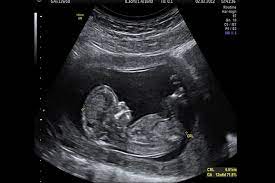

Si hay malformaciones graves si falta alguna extremidad o incluso adelantar el sexo del bebé porque ya están formados los genitales externosLa embarazada suele entrar en una etapa de mayor estabilidad menos náuseas y. A pesar de que coloquialmente se dice que un embarazo humano dura 9 meses la realidad es que son 10. Psicomotricidad - A partir de los 11 meses si se le coge por los brazos intenta dar sus primeros pasos.

11 semanas de embarazo. Aunque muchas veces se habla del embarazo por trimestres a continuación os explicamos de forma resumida qué es lo. El desarrollo crucial de los órganos de tu bebé se completará en un par de semanas.

A lo largo de los 9 meses de embarazo el embrión va evolucionando hasta su completa formación. Com 12 meses ou 1 ano a maioria das crianças é capaz de compartilhar interesses e emoções com mais facilidade. 10 meses de embarazo. Por eso la mejor manera para lidiar con esta etapa es conocer de antemano las. Su piel es tan finita. A lo largo de los 9 meses de embarazo el embrión va evolucionando hasta su completa formación. Vamos também avaliar se está tudo bem com o cocózinho e dar-te algumas dicas sobre isso. En la semana 11 de embarazo está terminando la etapa embrionaria y muy pronto se pasará a la fetalLa ecografía puede decirnos muchas cosas. Síntomas y molestias desde la semana 37.